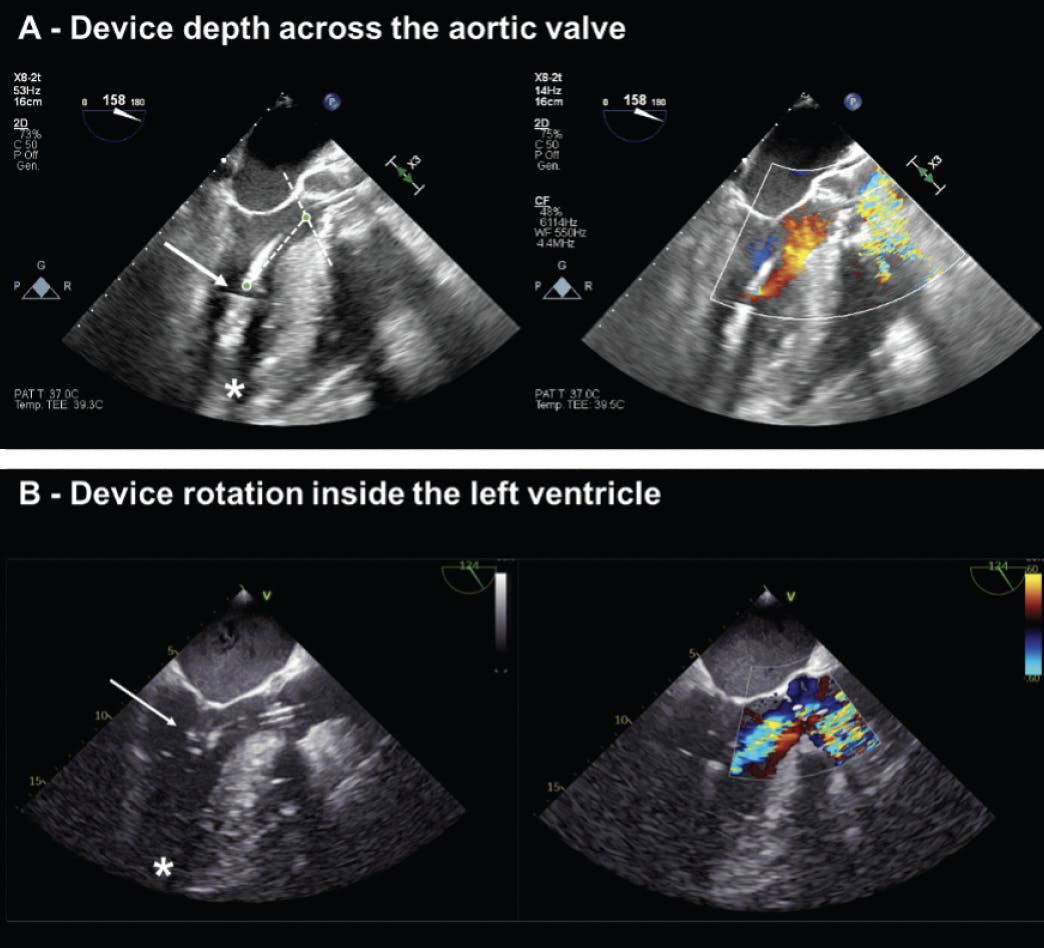

Device depth assessment. Optimal device depth across the aortic valve is pivotal to ensure proper device functioning. It can be verified by a position aortic waveform and a pulsatile motor current waveform on the Automated Impella Controller (AIC), and it can be confirmed using different imaging modalities. In the catheterization laboratory, a standard 30° right anterior oblique (RAO) fluoroscopic view is generally used to monitor device insertion inside the LV and to initially evaluate device depth, optionally with the addition of a pigtail diagnostic catheter or a guidewire to mark the aortic valve plane. Echocardiography provides more immediate and accurate assessment of device depth. In a three-chamber view (Figure 2A), the distance from the mid-inlet to the aortic valve should be approximately 3.5 cm, while the distance from the teardrop artifact to the aortic valve should be approximately 4 cm. The outflow area waterfall artifact should appear well above the aortic valve.

Figure 2. Assessment of device position at mid-esophageal three chamber views. Example of an optimally positioned device (A). The inlet area (arrow) is toward the LV apex (asterisk), the distance of the inlet from the aortic valve plane is approximately 3.5 cm, and the outlet area is well above the aortic plane. An example of malrotated device (B). The inlet area is away from the LV apex (asterisk) and just below the mitral valve (arrow), while the pigtail is toward the posterior papillary muscle there is also significant associated aortic regurgitation.

Device rotation assessment. Optimal device rotation within the LV is defined by the position of the catheter inflow tip toward the LV apex. Recently, we proposed the term “malrotation” to label those cases in which, despite a proper depth of the device across the aortic valve, the catheter inflow was oriented away from the LV apex, and toward the mitral valve apparatus and the LV inferolateral wall (Figure 2B).7,8 This issue appears common, generally overlooked, and associated with adverse clinical outcomes.7,8 Assessment of correct device orientation relies on imaging, because malrotation does not generally trigger position alarms on the AIC, although it may also occasionally manifest with suction alarms or hemolysis. The use of a standard 30° RAO fluoroscopic view during device implantation might be misleading (Figure 3) and a dedicated fluoroscopic protocol encompassing multiple views is currently under development. Echocardiography can easily identify device orientation inside the LV combining standard bidimensional three-chamber (Figure 2), and four-chamber views or with the use of tridimensional reconstructions.